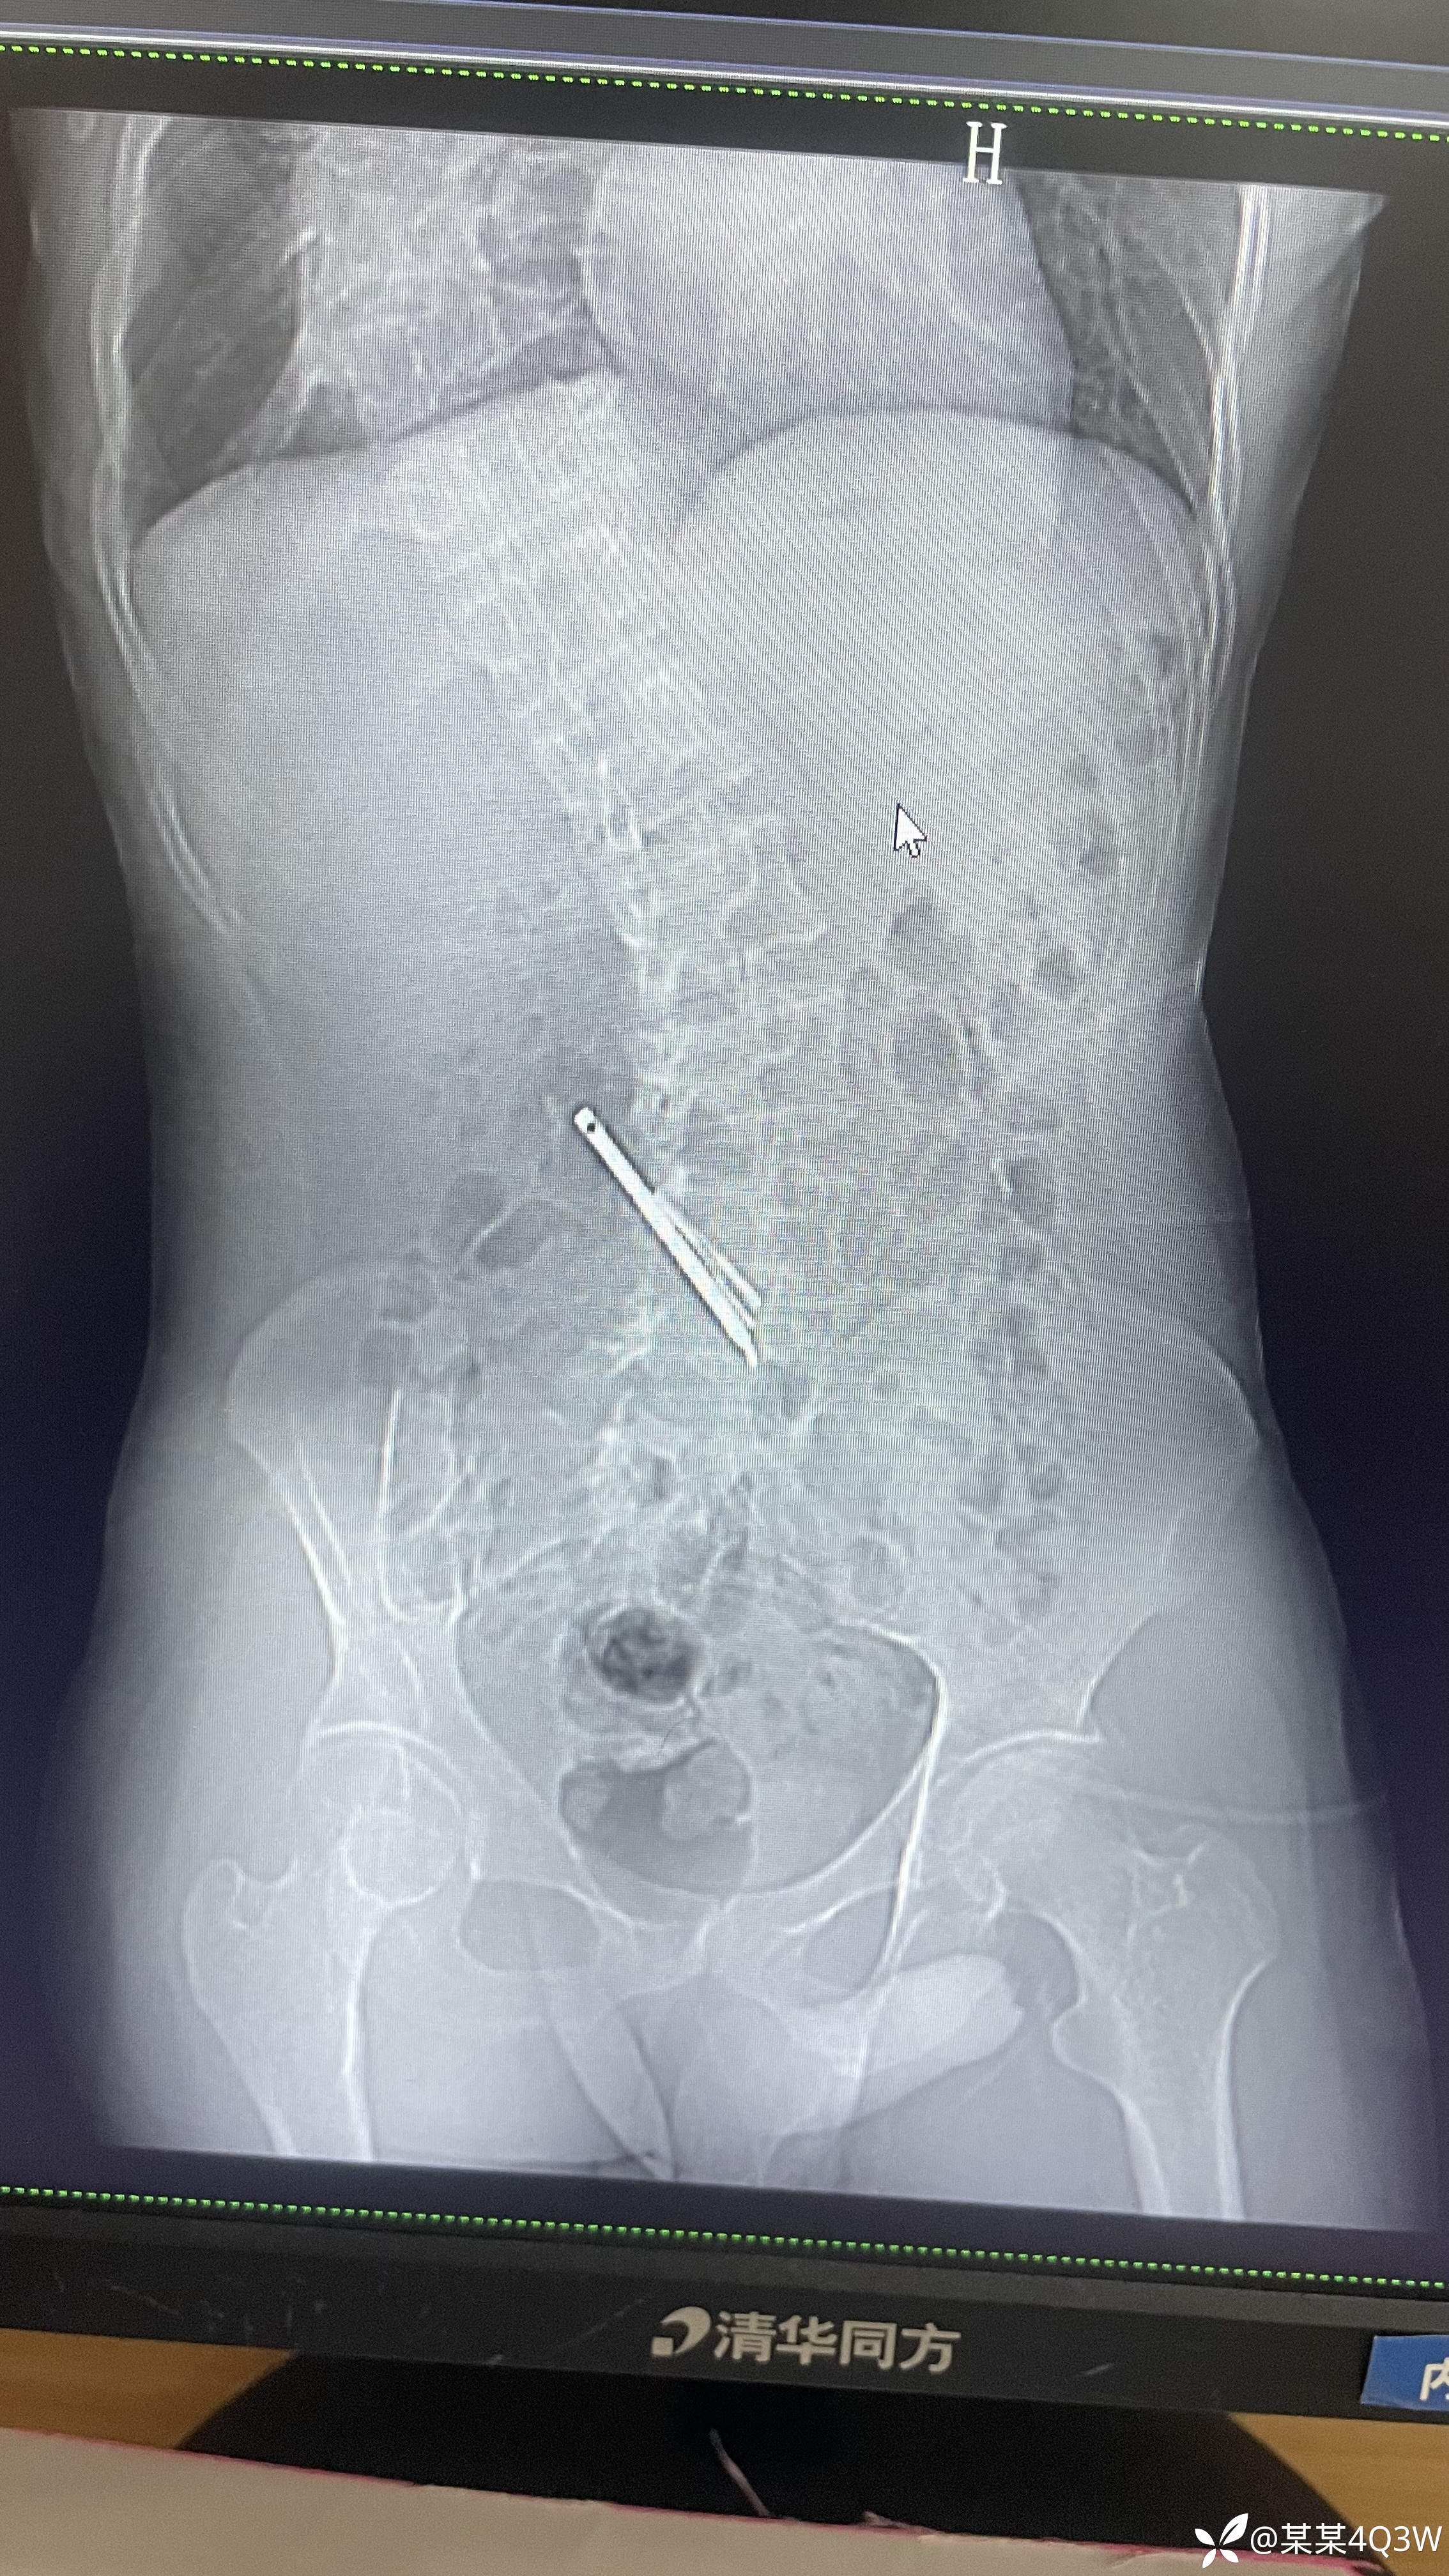

病例消化道异物

消化道异物 (95)